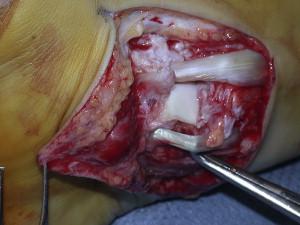

This patient has a lateral subtalar joint dislocation. The posterior tibialis tendon is the most common structure preventing successful closed reduction.

Subtalar dislocations are hindfoot dislocations that result from high-energy trauma. The diagnosis is made clinically and confirmed with orthogonal radiographs of the foot. A lateral subtalar dislocation has been associated with fractures of the cuboid, anterior calcaneus, lateral process of talus, and the fibula. Treatment is a trial of closed reduction but may require open reduction given the several anatomic blocks to reduction. Blocks to a successful closed reduction of the lateral subtalar dislocation include medial-sided structures such as the posterior tibialis tendon (most common), flexor hallucis longus, and flexor digitorum longus.

Illustration A shows a posterior tibialis tendon preventing successful reduction of a lateral subtalar joint dislocation. Illustration B is the radiograph of the ankle demonstrating a medial subtalar dislocation.